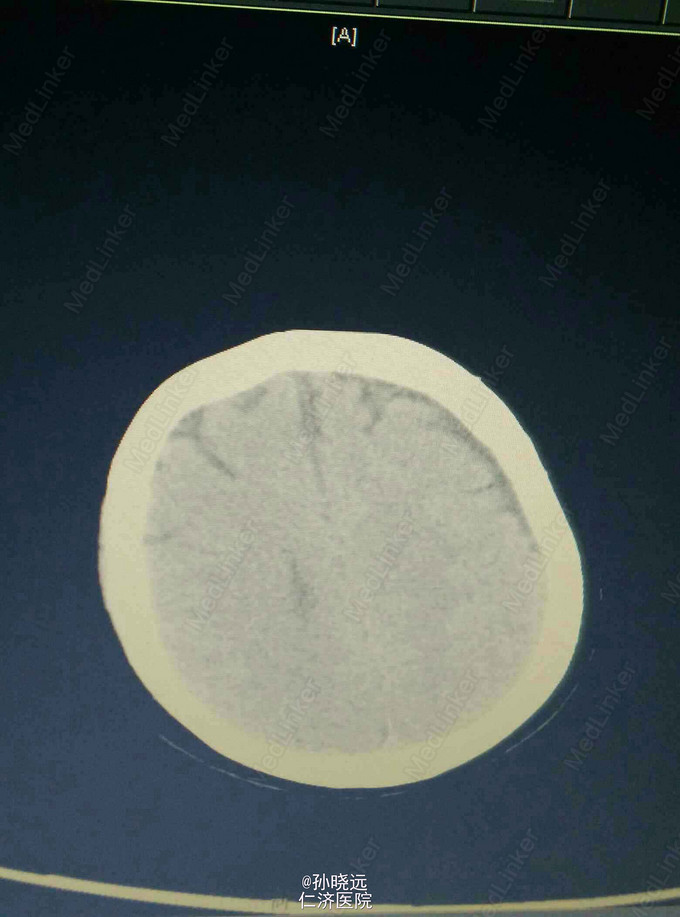

中年女性。主诉:头晕三天,发热伴神志不清1天。 患者于三天前出现持续性头晕,无恶心、呕吐,无视物旋转,来院就诊,查头颅MRI未见异常,予桂哌齐特、长春西汀、硫辛酸治疗,症状无好转。1天前出现高热,最高39.5℃,无咳嗽、气促,再次来院就诊,查血常规:WBC:5.85*10^9/L,N:71.8%,CRP正常,予退热,阿奇霉素等治疗,今日凌晨出现神志不清,无抽搐、恶心、呕吐,头颅CT示两侧颞底部不规则斑点样密度增高影并周围低密度灶,考虑脑炎合并灶性出血,予更昔洛韦、醒脑静、喜炎平、奥美拉唑、甘露醇治疗。后出现氧饱和度下降,予气管插管有创呼吸机辅助通气。 既往史:曾有高血压病史,未应用降压药。

诊断:脑炎。脑出血。 治疗:甲强龙抗炎,更昔洛韦,青霉素钠抗感染,降压,甘露醇、甘油果糖、白蛋白、拖拉塞米里降颅压,呼吸机辅助通气等对症治疗。

腰穿是: 脑脊液生化:葡萄糖:12.18mmol/L,CL:110.9mmol/L,蛋白:222.4mg/dl, 脑脊液常规:淡黄,微混。红细胞:1000*10^6/L,白细胞:1059*10^6/L,潘氏试验阳性(++++),嗜中性粒细胞12%,淋巴细胞:80%,单核细胞8%,凝块无,细菌未找到。 予加用血必净,加强抗感染等治疗。 患者目前仍昏迷,正进行高压氧仓治疗。这是最近一次复查的头颅CT。